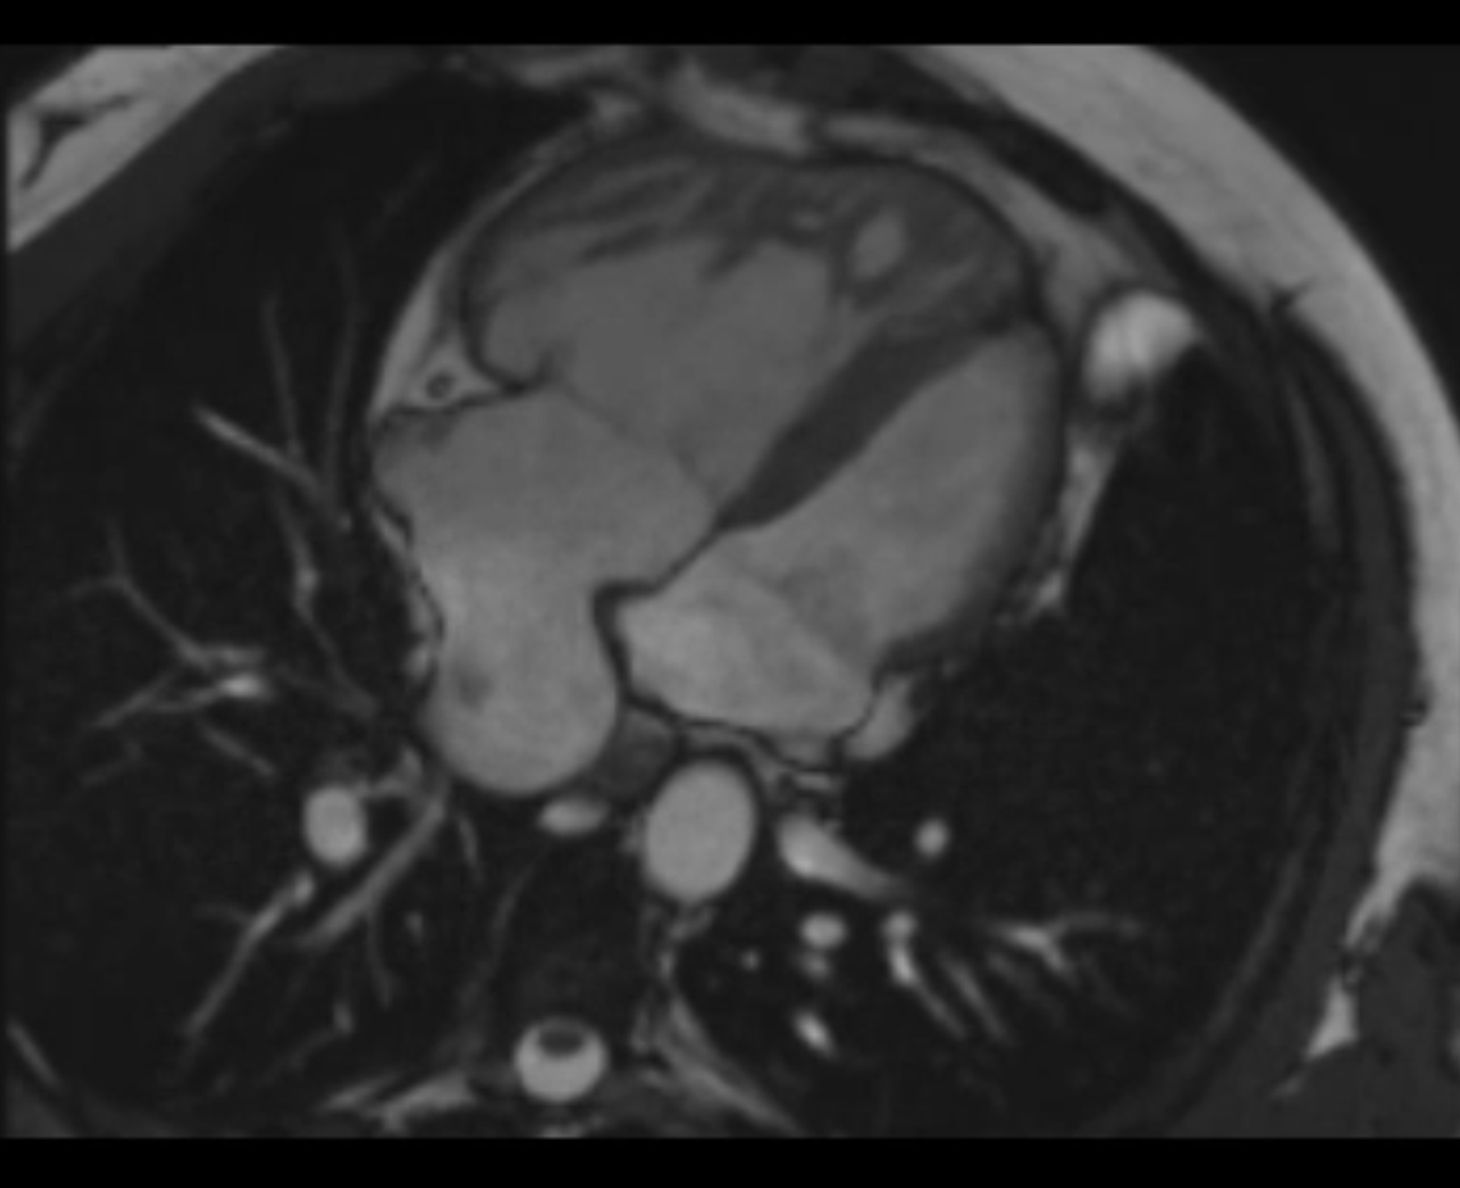

Die kardiale MRT ermöglicht in allen Altersstufen eine hervorragende Darstellung des Herzens und der Gefäße. Sowohl Struktur als auch Funktion lassen sich mithilfe dieser Untersuchungsmethode umfassend beurteilen. So können Fehlbildungen des Herzens und der Gefäße auch bei Säuglingen und Kleinkindern (in Narkose) sehr genau dargestellt werden. Komplexe Herzfehler können den Chirurgen mittels moderner Rekonstruktionstechniken als virtuelles oder reales 3D-Modell zur Verfügung gestellt werden. Zur Anwendung kommen modernste MRT-Scanner (1,5T u. 3T) der Fa. Siemens Healthineers.

Die Kombination der unterschiedlichen MR-Verfahren ermöglicht eine umfassende anatomische Darstellung der Struktur des Herzens und der großen Gefäße:

• Darstellung der Herz- und Klappenfunktion

• Bestimmung von Kammergröße und – volumina

• Darstellung der Herzkranzgefäße

• Messung der Blutversorgung des Herzens

• Stoffwechseluntersuchungen des Herzmuskels